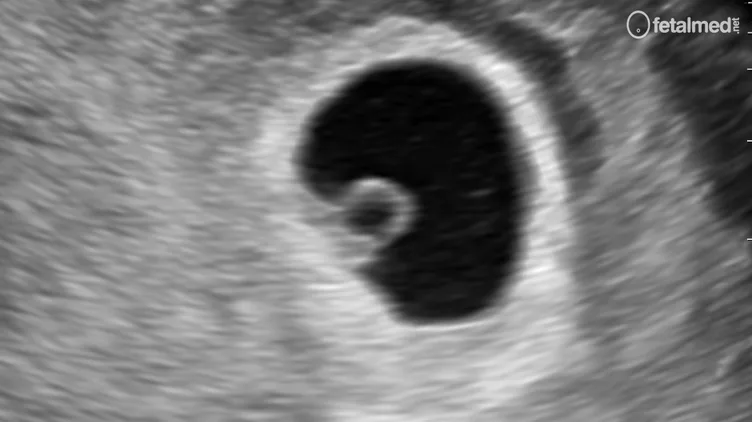

No início da gestação, antes que o embrião seja visível ao ultrassom, o diâmetro médio do saco gestacional (DMSG) é o principal parâmetro para estimar a idade gestacional e correlacionar com os níveis séricos de β-hCG.

O diâmetro médio do saco gestacional é calculado pela média das três dimensões internas do saco (longitudinal, anteroposterior e transversal). A taxa de crescimento médio do saco gestacional é de aproximadamente 0,9 mm por dia. O saco gestacional pode ser visualizado por ultrassonografia transvaginal a partir de níveis de β-hCG acima de 1.100 UI/L.

- Vesícula vitelínica: visível a partir de DMSG de 6,7 mm (β-hCG ≥ 5.800 UI/L)

- Atividade cardíaca: visível a partir de DMSG de 14,0 mm (β-hCG ≥ 24.000 UI/L)